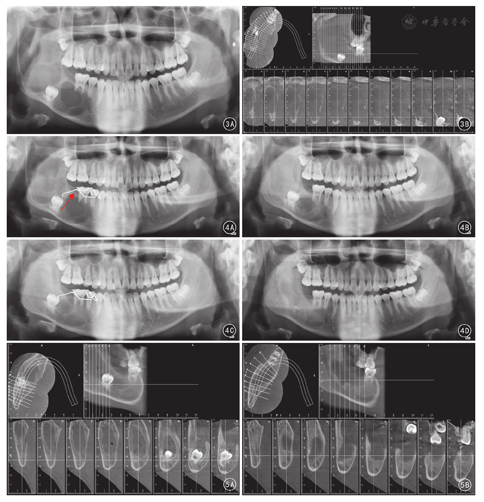

典型病例:患者男,17岁,因右面部肿胀4个月入院。专科检查:颜面部不对称,右面部肿胀,右下唇麻木,张口轻度受限,开口型及咬牙合基本正常,右下颌升支及右下颌磨牙区前庭沟膨隆,触诊有"乒乓球"感。右下颌牙齿无松动。曲面体层X线片示:右下颌骨大型囊性占位,边界清楚,上自乙状切迹,下至下颌角,前达44根尖区,囊腔内下颌下缘牙齿1枚。口腔锥形束CT示:右下颌骨大范围骨破坏,下颌升支及44至下颌角区仅剩余部分骨皮质。根据影像资料,46远中存在分房间隔,确定开窗口选择在此处牙槽嵴顶。治疗方法:Ⅰ期采用局部麻醉下开窗减压术,于46远中做一直径约2 cm的切口,见牙槽嵴吸收明显,暴露囊壁后切取部分送病理学检查。吸尽囊液,打通囊腔间隔,尽量将囊壁与开窗口黏膜缝合,反复冲洗囊腔,碘仿纱条填塞并自开窗口引出。1周后制作带卡环的囊肿塞。嘱患者每日餐后自开窗口冲洗囊腔。Ⅰ期术后每月复诊进行临床及影像学检查,1年患者面形基本恢复且囊腔缩小明显,20个月行Ⅱ期刮治术。Ⅱ期手术自Ⅰ期手术的开窗口进入囊腔,刮尽残余病变组织并拔除囊腔内牙齿;开窗口予以严密缝合。术后继续随访,口腔锥形束CT可见囊腔继续缩小,至术后24个月可见仅开窗口下方残余一碟形缺损,余囊腔被新骨充填。见图2, 图3, 图4, 图5。